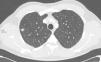

Presentamos el caso de un varón de 46 años con enfermedad renal crónica terminal secundaria a nefropatía por reflujo, trasplantado renal de donante cadáver hace 10 años y bajo tratamiento inmunosupresor con prednisona, tacrolimus y micofenolato sódico. Acude a su control rutinario totalmente asintomático, sin clínica respiratoria ni infecciosa sospechosa y con una exploración física no relevante. En la radiografía de tórax de control se objetiva una lesión ovoidea en el segmento posterior del lóbulo superior derecho (LSD) de 12mm de diámetro, no observada en el control previo un año antes. Se decide completar el estudio para filiar la lesión con TAC de tórax, donde se describe un nódulo pulmonar indicativo de neoplasia en el LSD (fig. 1), compatible con un estadio IA (T1a N0Mx). En el estudio PET se mostraba una captación patológica de la lesión descrita por lo que resultaba sospechosa de malignidad. Se decide realizar la exéresis quirúrgica del nódulo mediante una segmentectomía atípica con intención diagnóstica y terapéutica.